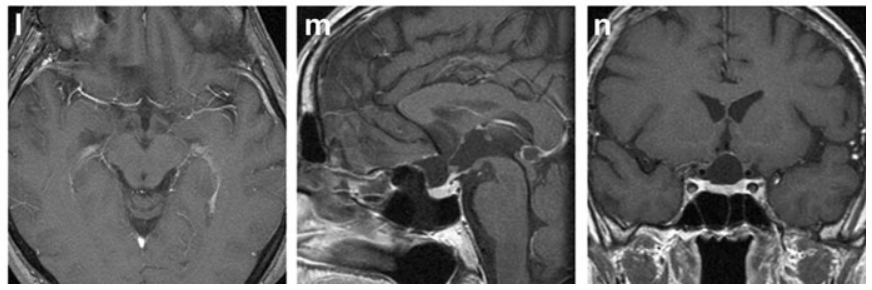

l–n 术后39个月增强T1加权MRI,均未见肿瘤残留或复发